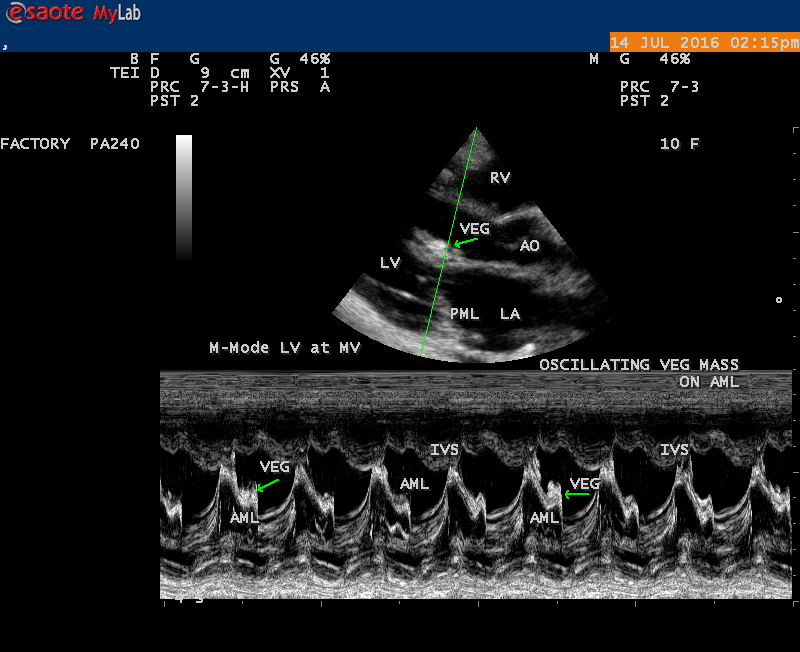

Vegetation

The most common and direct evidence of infective endocarditis is the vegetation and it begins as a microscopic focus of infection and gradually grows into a conspicuous mass. It is typically an irregularly shaped, highly mobile, echogenic mass attached to the free edge of a valve leaflet ( most commonly at the coaptation line) and tends to develop on the ‘upstream’ side of the valve leaflets ( ie, the ventricular side of aortic valve and the atrial side of mitral and tricuspid valves. They may be seesile or pedunculated, but usually has an oscillating or fluttering motion, a typical feature of most vegetations. Vegetation move with the leaflet in a more chaotic (‘oscillating’) manner and it may prolapse through the valve into the LV (left ventricle) as it opens as shown in Figures 3, 4 and 16 and into LA (left atrium) as it closing (Figure 5 and 6) . The mass of vegetation is typically homogeneous with echogenicity similar to that of the myocardium. The infectious process often alter the valvular structure and function. Extensive involvement of the leaflet may result in chordal rupture, leading to severe regurgitation as shown in Figure 21 . Direct and typical signs of RMCT (ruptured mitral chordate tendineae) were chain-flail or whiplash-like changes and had an incidence of 86.7%, causing severe regurgitation and mitral chordal rupture is the leading cause of flail mitral leaflet[30]. A large vegetation may obstruct the valve orifice as shown in Figure 1 and 2 , sometimes termed as “obstructive-type bacterial endocarditis” and producing a functional valve stenosis ( Ping-Pong mitral stenosis [31]) similar to left atrial myxoma as shown in Figure 29.

The shape and size of vegetation are quite variable and mostly it is polypoid [32]. The typical vegetation is a ‘sessile’ or ‘ pedunculating’ valve – attached mass. A ‘sessile’ vegetation had to be completely attached to the valve as shown in Figures 34 and 35 in a 63- year old male, in which a large vegetation is attached to the atrial side of anterior mitral leaflet [33-Figure 13.3-A], producing severe mitral regurgitation as shown in Figure 36 and a mobile vegetation showed a pedunculating part prolapsing into the ventricle as shown in Figure 3 and 4 or atrium as shown in Figure 5 [33-Figure 13.1] in a 10-year old female child. A vegetation was considered as ‘definite’ when shaggy echoes in the M-mode study as shown in Figure 20 . and a corresponding mass without restricted valve motion in the two-dimensional echocardiogram were found as shown in Figure 16 and 30 [33-Figure 13.7]. The vegetation vary in size, often being just a few mm and sometimes reaching to 2-3 cm. A vegetation must be atleast 3 to 6 mm in size to be reliably seen. The mean size of vegetation was 0.6 mm (range 3 to 28) and vegetation > 10 mm in diameter was defined as ‘large’ and those ≤ 10 mm in diameter was defined as ‘small’ and ≥ 15 mm is ‘very large’. Vegetations resulting from fungal infections (candida, aspergillus) are usually much bigger than bacterial vegetations and can be so big to be mistaken for a cardiac tumor. The large vegetations are at increased risk for embolic complications [34], especially on the anterior leaflet of the mitral valve with mobility [35]. A vegetation size of 3.2 x 4.4 cm is called as ‘giant vegetation’ on the mitral valve with a fibrillary appearance of the mass [36- Figure 3] as shown in Figure 1 is an important predictor of embolic phenomena in patients with infective endocarditis causing severe mitral regurgitation as ‘Duck’ shaped jets (Figures 24 and 25 ), disorganized (Figure 21) and sometimes the regurigitant jet splits into two components as one into LA and the second one into LV simultaneously as a bileaflet jets (Figure 10 ) similar to bileaflet structure of AML with vegetation masses (Figure 9 ) . The size of the largest vegetation reported on the mitral valve in the literature in patients with bacterial endocarditis is 7x4 cm[37]. In a study of Nunes, et al[38], vegetation size >13 mm was the only independent predictor of mortality, but some studies [39],[40] did not had an increased embolic risk in patients with vegetation focused only on its presence and size and not on their location. Embolic complications may occur in infective endocarditis(20.6%)and were not more prevalent in the groups with large vegetations [41]. However, Wong, et al [42] found an increased need for surgery in patients with a large vegetation (>10 mm).